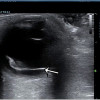

Vitreus adalah cairan transparan berbentuk gel yang berfungsi untuk mempertahankan struktur bola mata. Vitreus tersusun dari 98–99% air. Sisanya adalah kolagen, asam hyaluronat, dan elektrolit. Perdarahan pada kavum vitreus disebut sebagai perdarahan vitreus. Pasien dengan perdarahan vitreus tidak merasakan nyeri tetapi mengeluhkan floaters, pandangan berkabut atau berbayang, dan gangguan tajam penglihatan sesuai banyaknya perdarahan pada aksis visual.[2,3]